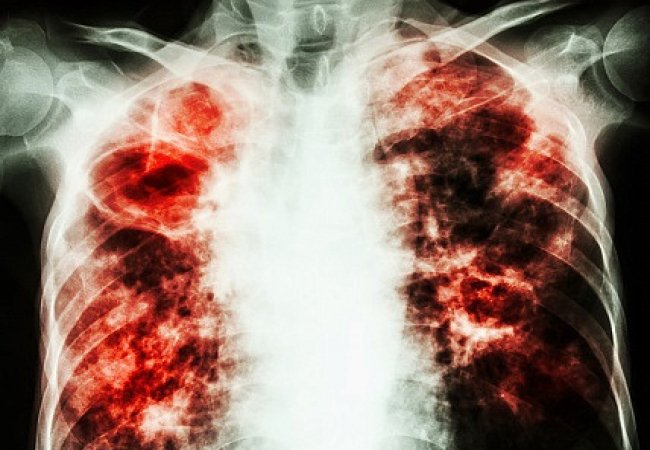

Як прогнозують експерти Всесвітньої організації охорони здоров’я, через пандемію коронавірусу епідемія туберкульозу може прогресувати. Однією зі складових успішної боротьби з хворобою є пріоритетність лікування пацієнтів в умовах стаціонару, де можна ізолювати їх від соціуму.

«На думку фахівців Всесвітньої організації охорони здоров’я, через коронавірус епідемія туберкульозу загостриться, адже зараз важко діагностувати хворих: прийом пацієнтів у поліклініках обмежений, профогляди не проводяться, хворі залишаються вдома. Натомість дуже важливо своєчасно виявляти туберкульоз, проводити флюорографію серед населення, адже, доки хворий не кашляє, він не є небезпечним для населення і вилікувати його легше. Зараз більшість виявлених випадків – це занедбані пацієнти, які кашляють кілька місяців, а то й років», – розповів медик.

Він поінформував, що туберкульозом інфіковані 90-95% дорослих і половина дітей шкільного віку. Хвороба ж розвивається, зокрема, у разі послаблення імунітету організму. На щастя, діти хворіють не так часто, як дорослі.

Підступність туберкульозу ж полягає в тому, що часто він може проходити на початкових стадіях безсимптомно, або з такими неспецифічними симптомами, як втрата ваги, погіршення апетиту, болі в хребті, невисока температура, захриплість горла тощо.